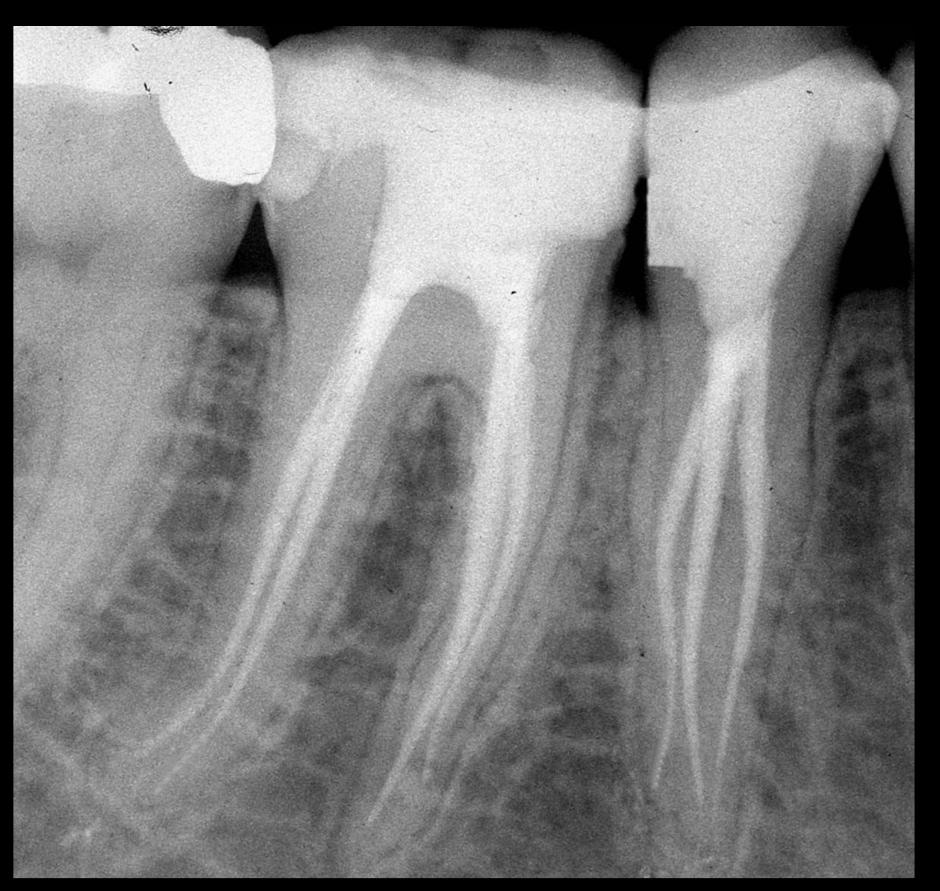

La terapia endodontica prevede l’asportazione della polpa necrotica dalla camera pulpare e dai canali radicolari, la disinfezione e la sagomatura dei canali e la loro otturazione mediante specifici materiali inerti.